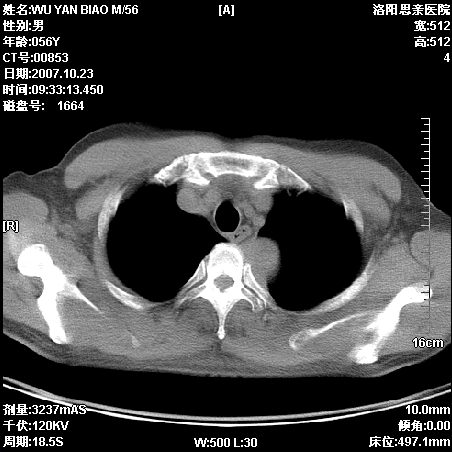

后上纵隔占位,与肺交界清,宽基底附着脊柱,密度均匀,局部骨质无明确改变.

考虑;神经源性肿瘤,---起源交感n链?,不除外肠源性囊肿.

与纵隔关系密切,密度均匀。只能考虑:后纵隔神经原性肿瘤!

后纵隔神经原性肿瘤可能性大,孤立性胸膜间皮瘤待排.

1、病灶在后纵隔脊柱旁沟内,此处是神经原性肿瘤的好发部位

2、病灶边缘光滑整齐,更说明病灶来于纵隔,由于有胸膜的包裹所以才导致这么光滑的边缘

3、病灶内的密度均匀